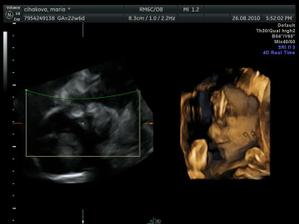

Pat a Mat 24 t.t. 4D

...noo trvalo to dlho, chlapci sa nechceli ani fotiť ani natáčať...takže máme jedna vydarenú foto a potom iba zadočky a pod.....🙂))

ničmenej, bolo to zlaté vydieť ako sa smejú a otvárajú pusinky 🙂)